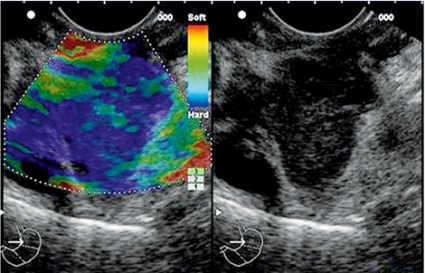

Undersökningen går till på samma sätt som en ordinär gastroskopi med samma förberedelser, och den tar mellan 15 och 60 minuter att genomföra. Elastografi är under utveckling och skulle kunna underlätta tumördiagnostiken genom bedömning av vävnaders konsistens (Figur 2).